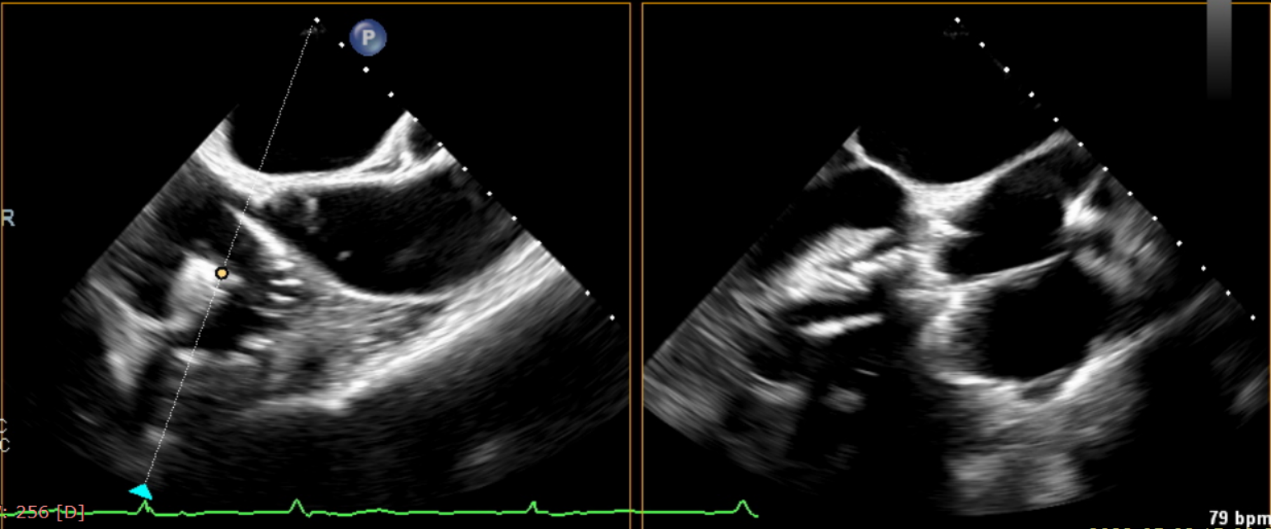

術(shù)前超聲提示大量三尖瓣反流

術(shù)后超聲提示僅殘余輕微瓣周漏